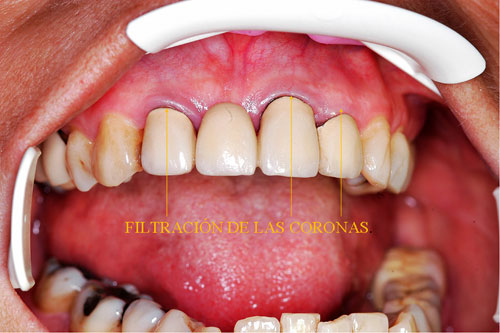

RESUMEN Mostración del Protocolo en R. O. y su desarrollo clínico. DESARROLLO Quienes realizamos Rehabilitación Bucal Integral desde muchos años atrás, siempre hemos buscado un protocolo coherente que nos permitiera ordenar el pensamiento cuando nos encontramos con aquellos caóticos casos donde marearse en la resolución es fácil y frecuente. PROTOCOLO DE ALONSO Sintéticamente consiste en otorgar al Sistema en primer término: Desoclusión en Lateralidades y Propulsiva de los sectores posteriores, mediante la construcción de la Guía Anterior tanto en los Provisorios como en los Definitivos, basados en el Encerado de Diagnóstico. PROTOCOLO PRÁCTICO (BASADO EN D.A.T.O.) Diagnóstico: clínico, radiográfico (donde no es necesario extenderse) y de laboratorio, donde mediante un encerado diagnóstico y otro de trabajo, conoceremos la fiel réplica de la boca del paciente antes de destruirse y los medios para reconstruirla basados en los procedimientos que podemos realizar en la cera. PRESENTACIÓN DEL CASO Se presenta la paciente derivada por un compañero a fin de consultar acerca de un primer molar superior izquierdo, a quien el Periodoncista aconsejaba realizar una radectomía debido a la pérdida ósea distal que dicha raíz presentaba. Dicha observación hace que decidamos tomar una actitud más conservadora, explicando al enfermo las razónes etiológicas de la pérdida ósea, y aconsejando quitar dicha funda para colocar una provisional morfológicamente correcta, y simultáneamente re-endodonciar y realizar la terapia básica periodontal. Visión Global del Caso Se observa a la inspección clínica y radiográfica, varios puentes fijos filtrados, como así también amalgamas de plata recidivadas. Inversión de la Curva de Wilson.(2º Elemento a nuestro alcance para obtener Desoclusión Se procede entonces luego de realizar los correspondientes modelos de yeso mediante impresiones precisas de alginato con cubetas Rim Lock, a tomar un registro cráneo maxilar mediante un arco facial estático (Artex) que nos permita montar el modelo superior respecto del Plano de Frankfurt con el punto Gnation de referencia. Luego, haciendo uso de las Laminillas de Long , (buscar referencias en el libro del Dr. Alonso o bien en múltiples publicaciones personales en Gaceta Dental o Maxillaris, como así también en mi propia web: en los artículos : RELACIÓN CÉNTRICA o AJUSTE OCLUSAL, BASES FILOSÓFICAS DE UNA OCLUSIÓN ORGÁNICA), (www.dracuna.com o www.oclusión.es,) . Procedemos a obtener el Registro Inter Maxilar de OCLUSIÓN EN RELACIÓN CÉNTRICA, mediante el cual, montamos el modelo inferior respecto del superior. Montamos así, en un Artex totalmente ajustable, pués no contábamos en ese momento con ningún semiajustable disponible,(ya que estaban todos ocupados), ajustando el Ángulo de Bennet y la Inclinación de la Trayectoria Condílea en gradaciones personalizadas mediante registros de Propulsión y Lateralidades). Procedemos entonces al estudio de los modelos. DIAGNÓSTICO GENERAL Disfunción oral generalizada, provocada por alteraciones en la Oclusión, en la Operatoria Dental, en la Endodoncia, en la Periodoncia y en la Prótesis realizada en esta boca a través de los años. Filtración generalizada de fundas. DIAGNÓSTICO PROTÉTICO OCLUSAL Carencia de guía canina. Carencia de alineación tridimensional en guía anterior. Carencia de curva de Wilson. TRATAMIENTO SUGERIDO 1-Encerado Progresivo de Diagnóstico y Trabajo de Peter K. Thomas. HEMOS OBTENIDO: D.AT.O Hasta aquí, hemos solo observado los elementos de diagnóstico clínicos, radiológicos y de laboratorio, como para comenzar a trabajar. AUTOR: Colaboración: CASO PRESENTADO EN LAS SESIONES CLÍNICAS DEL ILTRE. COLEGIO DE DENTISTAS DE MÁLAGA. Ratificación del Protocolo en Rehabilitación Bucal a pesar de las incidencias propias de cada caso clínico. A propósito de un caso.

Observada la pieza clínica y radiograficamente, podemos ver una corona excesivamente sobredimensionada sobre un molar deficientemente endodonciado, que no solo muestra la pérdida ósea distal de la raíz en cuestión, sino también y producto de la mala endodoncia, un granuloma en la raíz mesial y en la furca.

Aconsejamos a la paciente realizar un estudio de toda la boca, ya que el molar en cuestión constituía apenas una muestra más de una odontología parcial, iatrogénica, y mal llevada, durante muchos años.

Realizamos fotografías de toda la boca y la correspondiente ortopantomografía apoyada por imágenes de laser visiografía seriada, estudio inicial mínimo necesario para diagnosticar el funcionamiento del SEG.